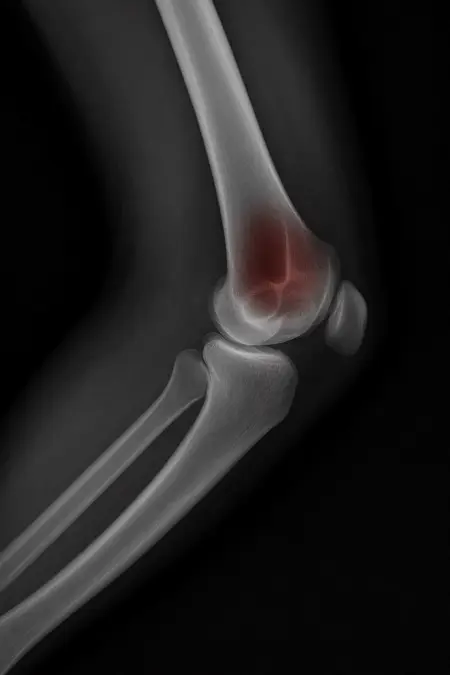

アートや写真の編集用に設計されたFlux Kontextのようなモデルを、医療画像、たとえば「単純な」骨折の赤色マーキングに使用できるか?

即答:面白い結果を出すが、過剰に反応し、医療ツールとしては信頼性に欠ける。これはアイデアを試すためのプロトタイプに過ぎない。

テスト結果:

- 偽陽性 ≈ 24%

- 骨折検出 ≈ 20%

感度モード(検出を優先、ノイズ多め)

- Euler、15ステップ、Karras

- Denoise:1.0

結果:

- 偽陽性 ≈ 80%

- 骨折検出 ≈ 86%

さらに攻撃的な設定(例:rk beta57、Denoise 1.0)では、**偽陽性100%、検出100%**という馬鹿げた結果に:すべてを赤で塗りつぶし、健常部もほぼすべて骨折と誤認する。未経験の目には区別がつかない。

Civitai用に作成した、100% AI生成の合成ミニデータセット(健康なX線10枚、骨折のあるX線10枚)でテスト:

- 健康な骨での偽陽性:100%

- 骨折検出:≈ 45%